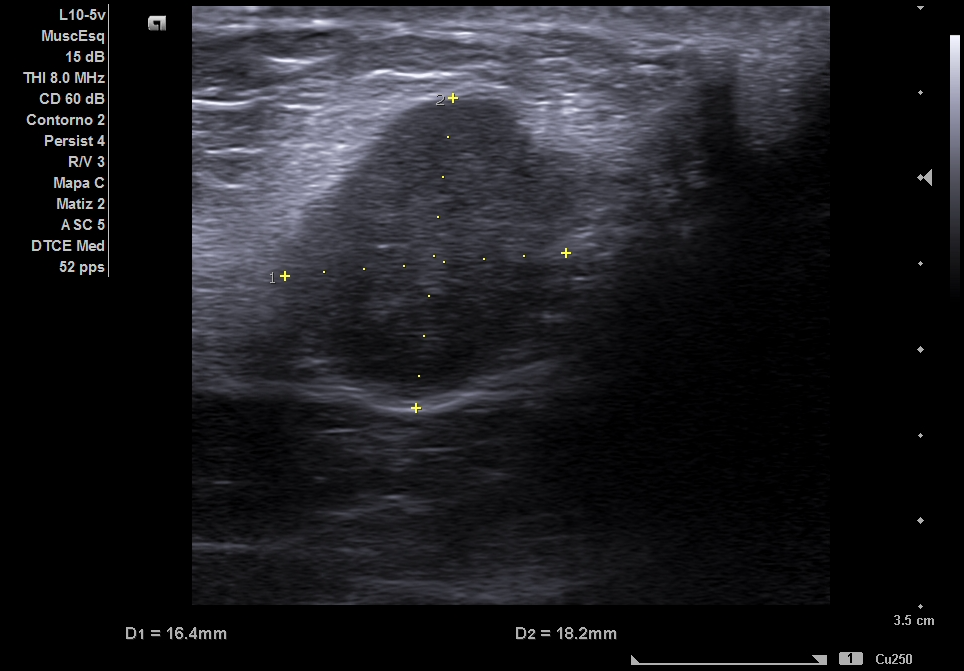

Ecografía clínica partes blandas y abdominal en Centro de Salud: dos nódulos subcutáneos hipoecogénicos, heterogéneos, lobulados y de bordes irregulares (16 x 18 mm), no vascularizados. Abdomen: sin signos patológicos relevantes ni Ascitis ni líquido en Douglas no adenopatías retroperitoneales. Completamos estudio de nódulos sospechosos de malignidad con tomografía abdominal y ecografía de partes blandas reglada.

Ecografía reglada de partes blandas: Nódulos subcutáneos e intrabdominales sospechosos de malignidad. La tomografía abdominal describe múltiples implantes sólidos peritoneales y en pared abdominal, compatibles con metástasis.